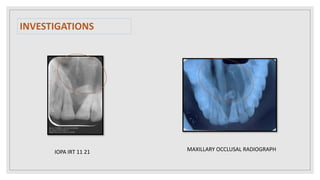

IOPA IRT 11 21 MAXILLARY OCCLUSAL RADIOGRAPH

INVESTIGATIONS IOPA IRT 1121 MAXILLARY OCCLUSAL RADIOGRAPH

• #18 IOPAR revealed no abnormality in coronal portion irt 11,21 and radicular portion shows Ill defined radiolucency of size measuring 2*3cm at apices of 11 21 with widening of PDL and loss of continuity of lamina dura. Internal structure is completely radiolucent showing two radiopaque masses resembling morphology of tooth suggestive of impacted supernumerary tooth. Occlusal radiograph revealed a ill defined radiolucency of size measuring 2*3cm is seen at apex of root irt 11,21 extending mediolaterally from distal aspect of 12 to mesial aspect of 23 region , anteroposteriorly from apices of 11,21 to line joining 16, 26, internal structreis completely radiolucent showing two radiopaque masses resembling the morphology of tooth suggestive of impacted supernumerary tooth. Effect on adjacent structures revealed displacement pf roots of 11,21 away from midline.